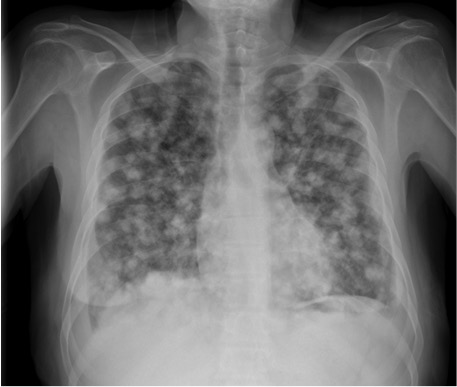

– Caso. Patrón nodular: opacidades redondeadas de muy pequeño tamaño normalmente difusas, con bordes netos, en número variable.

Causas:

- Granulomatosas: Tuberculosis miliar, Artritis reumatoide, Silicosis, Neumoconiosis, Sarcoidosis.

- Neoplasias: Metástasis (tiroides, riñón y melanoma).

- Otras: Proteinosis alveolar, Amiloidosis, Hemosiderosis, Microlitiasis alveolar.